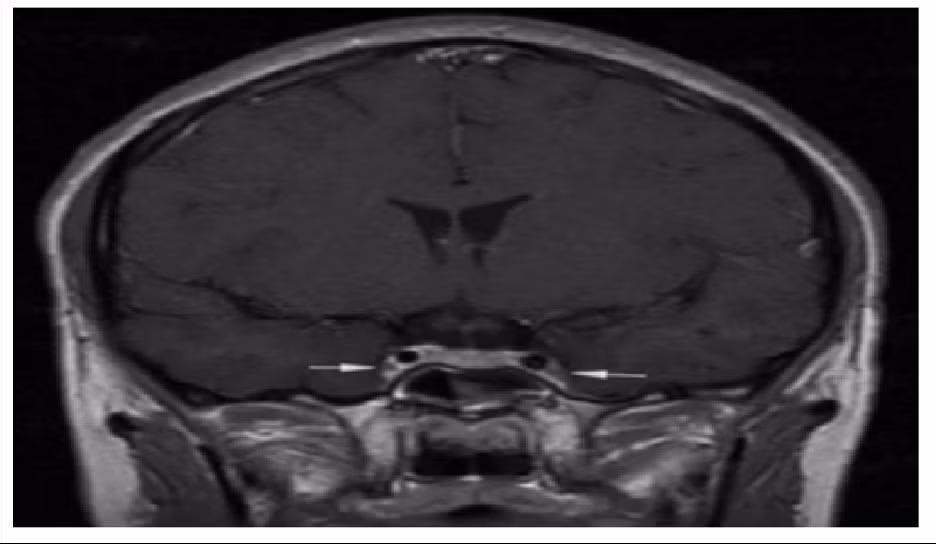

Vị trí mũi tên là viêm và co thắt động mạch cảnh trong 2 bên - Ảnh BVCC

Theo hồ sơ bệnh án, bệnh nhân khởi phát bằng viêm xoang cấp mủ, sau đó chuyển sang viêm tấy nửa mặt, rồi nhanh chóng xuất hiện rối loạn ý thức và co giật. Kết quả chụp cộng hưởng từ sọ não cho thấy: Phù nề lan tỏa, dấu hiệu điển hình của viêm tắc tĩnh mạch xoang hang - một tình trạng huyết khối nhiễm trùng ở nền sọ.